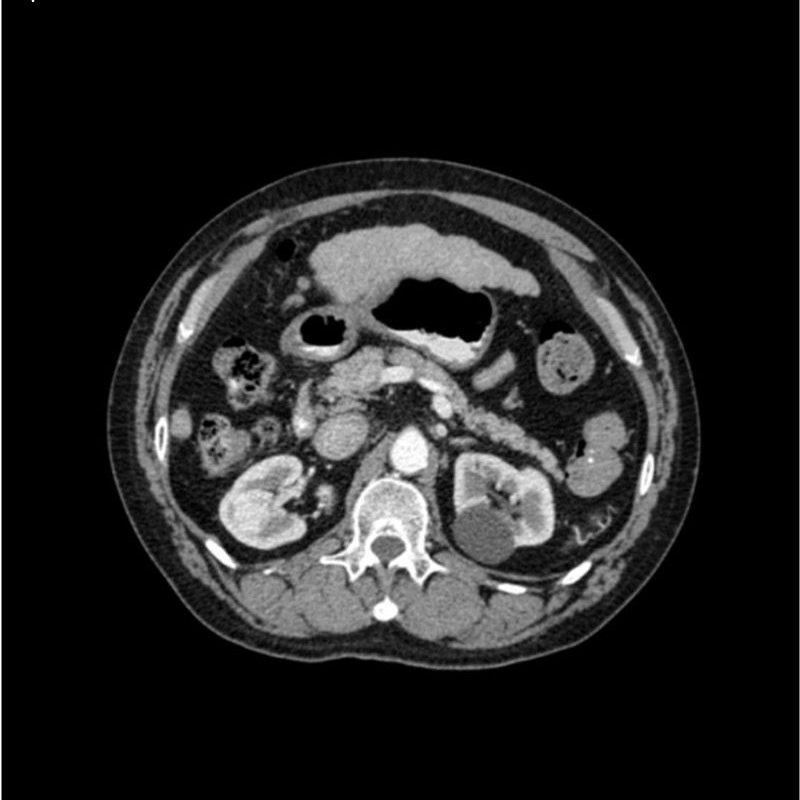

abdomen in portal venous phase. It covers the tenth thoracic vertebra to the third lumbar vertebra. The phantom represents an abdomen after cholecystectomy with small clips. The liver has typical signs of cirrhosis and there is an inferior vena cava filter implanted at the level of the third lumbar vertebra. Both kidneys have cystic lesions and there is a small kidney stone on the left side.

Realistic simulation of vasculature, bone and soft tissues, including the liver, pancreas, spleen, adrenals, kidneys, stomach, small intestine and colon.

- Liver cirrhosis

- cholecystectomy

- inferior vena cava filter

- kidney cysts

- kidney stone

- lymph nodes.